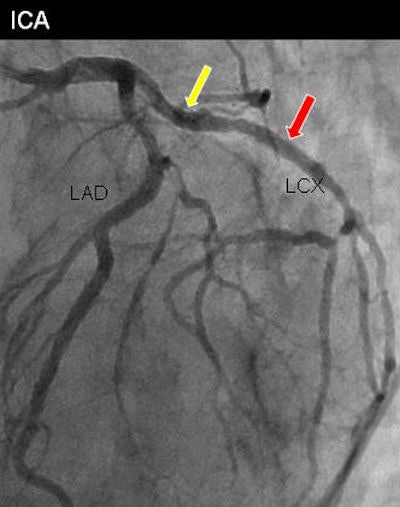

Digital subtraction CT angiography, like the conventional digital subtraction angiography (DSA) it is steadily replacing, works by subtracting precontrast from postcontrast-enhanced images to visualize anatomy in challenging environments where bone, soft tissue, or, in this case, metallic stents can create image artifacts.

Beginning with 897 patients with metallic coronary stents, the researchers performed subtraction coronary CTA in 387 patients, and they also analyzed the results of 99 patients (mean age, 54 ± 6 years) who underwent both subtraction CTA and invasive coronary angiography.

The CT images were evaluated by a cardiologist and a radiologist, and a second cardiologist also evaluated the invasive coronary artery images. They reviewed both the conventional and DSA images, calculating diagnostic accuracy and analyzing factors that affected subtraction effectiveness, Amanuma said. The mean heart rate was 54 ± 6 beats per minute, and the mean total radiation dose was 6.7 mSv ± 4.2.

There was a sharp improvement with the digital subtraction CTA protocol compared with conventional CTA, with invasive angiography as the gold standard. DSCTA scored higher in sensitivity, specificity, positive predictive value (PPV), negative predictive value (NPV), and accuracy, as indicated below.